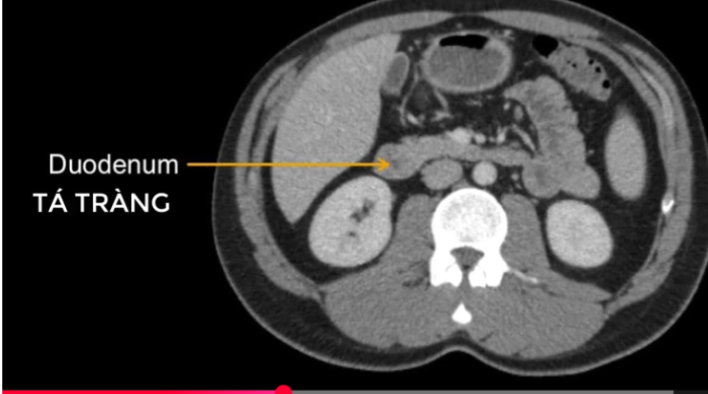

đt ngang?